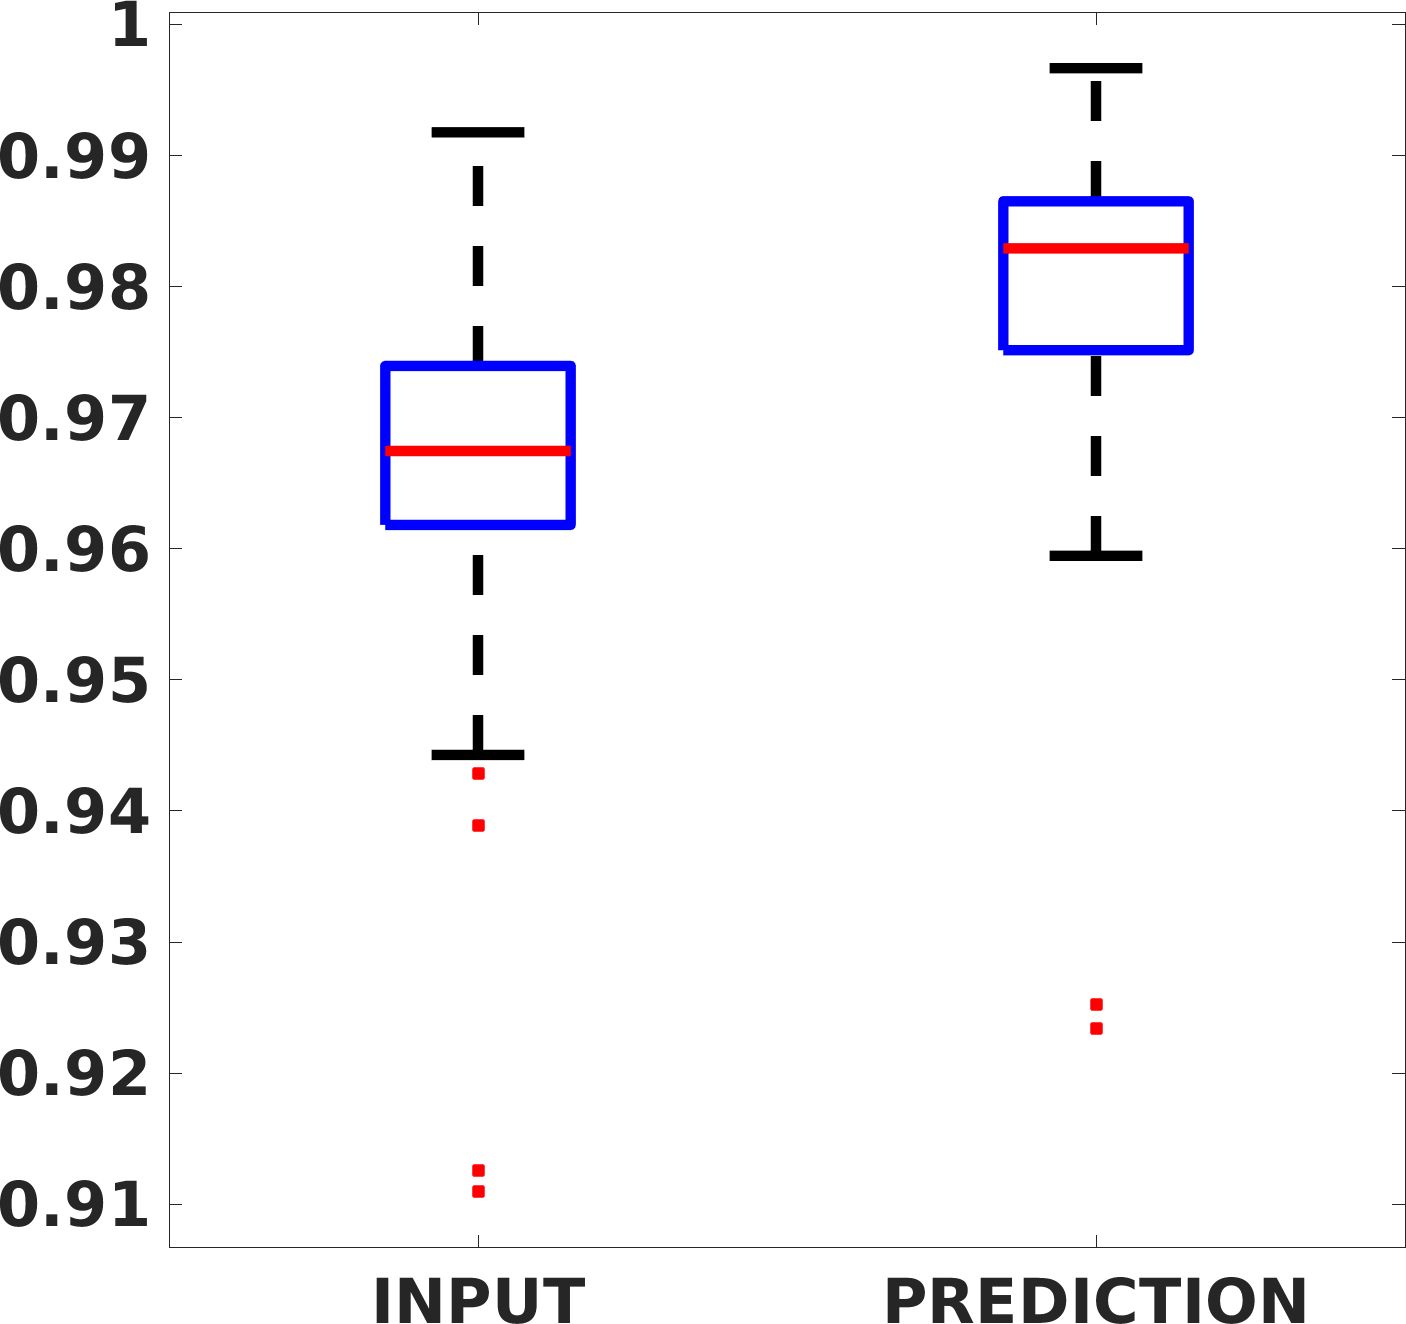

Fig. 7(a-b-c, left) shows the box plot of the statistics of the PSNR on three different anatomical districts, comparing the target images with the prediction and the cubic convolution, respectively. The metrics are computed on a data set of 200 images of the same district and with the same up-sampling factor. We report that the PSNR median value improves of on obstetric 2X raw images, on cardiac 2X raw images, and on abdominal raw 4X images.

Fig. 7(a-b-c, right) shows the histogram of the absolute value of the error with respect to the target image, of the prediction and Cubic convolution results, respectively. The histograms show the number of pixels where the prediction error is lower than 5 (i.e., the first bin of the histogram), which means very similar to the target when visually analysing the images. From the Cubic convolution to the predicted images, this value increases of on obstetric 4X raw images, on cardiac 4X raw images, and on abdominal 4X raw images.

Fig. 8 shows the box plot of the SSIM (a-b-c, left) and MAE (a-b-c, right) quantitative metrics, as performed for PSNR metric. Also, these metrics show that our method improves the results of Cubic convolution both in terms of average value and variability. For example, the SSIM median value improves of on obstetric 4X images and the MAE median value improves of on cardiac 2X images.